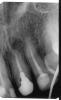

Hercule Опубликовано 25 ноября, 2012 Автор Поделиться Опубликовано 25 ноября, 2012 28 ноября :Апрель перед резекцией:Май после резекции:Июль после резекции: Скриншоты от 3Д Ссылка на комментарий